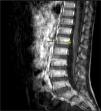

Myelitis was suspected due to the presence of hyperreflexia and tetraparesis, leading to initiation of a short course of oral corticosteroid therapy with a mild improvement of symptoms. Cranial and spinal magnetic resonance imaging (MRI) tests were requested. While the cranial MRI showed no abnormal findings, the spinal MRI revealed gadolinium uptake by the nerve roots of the cauda equina (Fig. 1), compatible with nonspecific radiculitis.

While the MRI findings tend to be nonspecific, studies of GBS in children5 report contrast enhancement of the spinal roots in most of the cases.